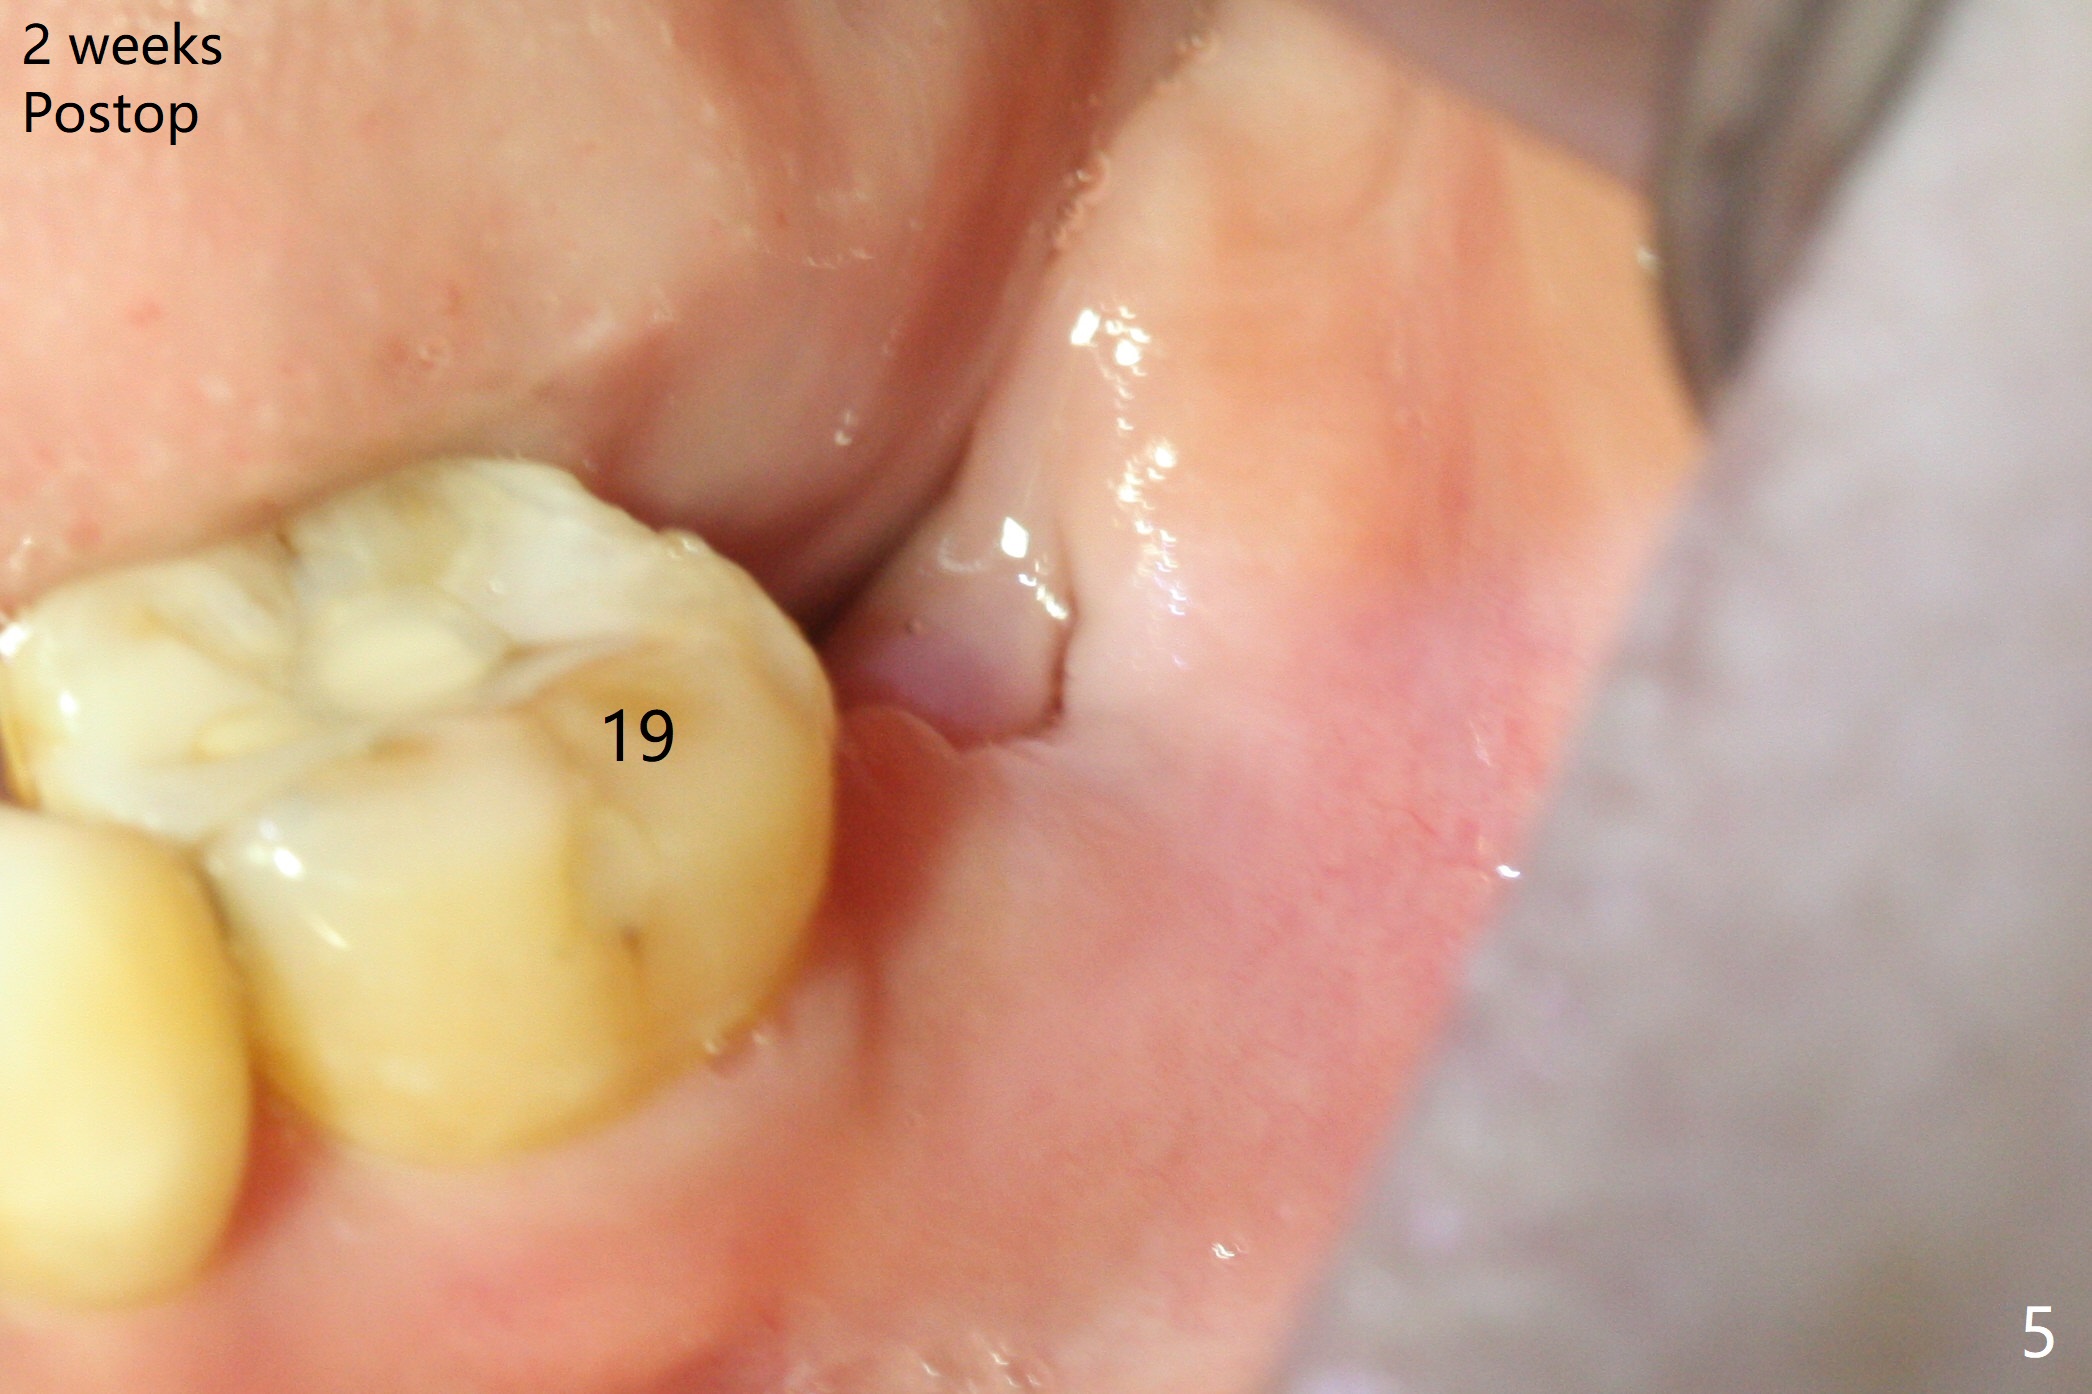

If the patient were not nervous and every step were followed by X-ray, light osteotomy in the bottom of the socket (flattening) may increase primary stability.  A larger implant (9 or 10 mm) is a solution.  The socket heals with disappearance of the fistula 2 weeks postop (Fig.5,6), but the ridge seems to have been reduced in width.  The patient return for follow up 4 months postop; bone graft appears to remain in the socket (Fig.7).  The ridge is apparently reduced further (data not shown).  The patient prefers to have implant placement 1 month later.  Take photos of the ridge buccally when the patient returns.  In fact the patient agrees to have guided surgery.  She postpones the surgery due to sickness for one more month.  Implant placement will occur 6 months post extraction.  The bone density should be higher than earlier.